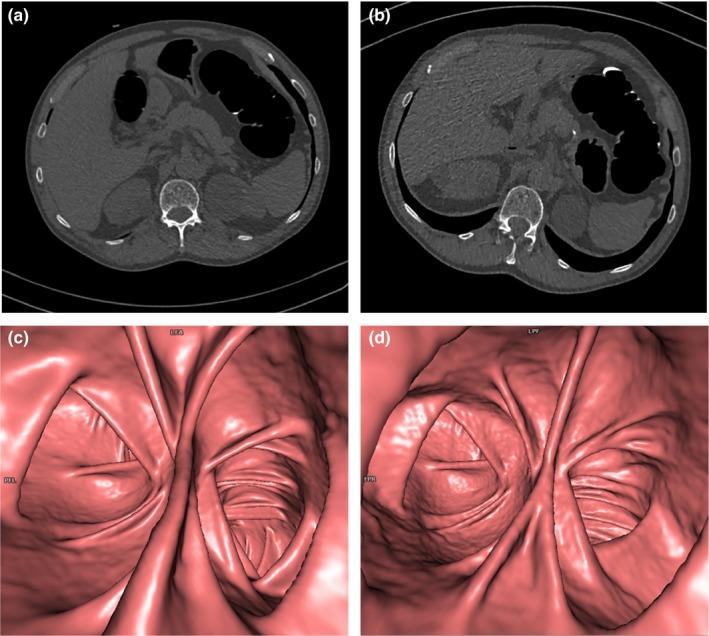

The mean effective dose of ULD-CTC was significantly lower than that of LD-CTC (0.98 and 2.69 mSv respectively, P < 0.0001) with an overall dose reduction of 63.2%. Image noise was comparable between ULD-CTC and LD-CTC (28.6 and 29.8 respectively, P = 0.09). There was no relevant difference when comparing image quality scores and polyp detection for both 2D and 3D images.

ULD-CTC的平均有效剂量显著低于LD-CTC(分别为0.98和2.69 mSv,P < 0.0001),总体剂量降低了63.2%。ULD-CTC和LD-CTC之间的图像噪声相当(分别为28.6和29.8,P = 0.09)。在比较二维和三维图像的图像质量评分和息肉检测时,没有发现相关差异。